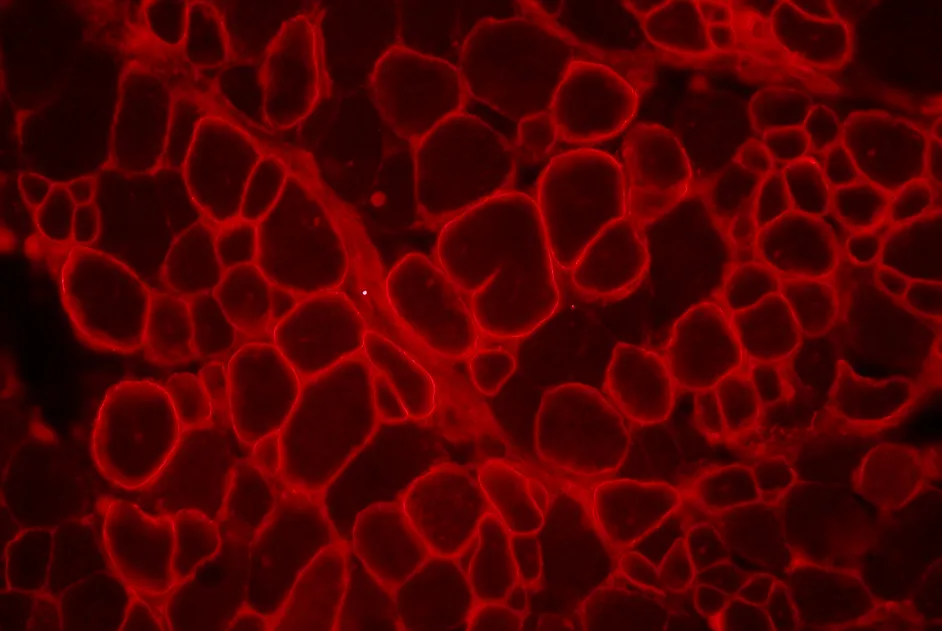

Dans un article publié en juillet 2013, une équipe française, soutenue par l’AFM-Téléthon, a testé une approche de trans-épissage in vitro. Pour cela, elle a administré dans des cellules de souris n’exprimant pas de dystrophine, un minigène de dystrophine de souris possédant une anomalie génétique associé à différents types de molécules de trans-épissage qui transporte une séquence normale de la dystrophine.

Les résultats ont mis en évidence l’efficacité du trans-épissage avec une restauration de la dystrophine et apporte ainsi la preuve de concept de l’efficacité de cette approche pour restaurer la dystrophine.

Cette approche a aussi permis d'obtenir de la dystrophine dans 2 modèles de souris de la DMD, la souris mdx (mutation dans l’exon 23 du gène de la dystrophine) et la souris mdx4Cv (mutation dans l’exon 53 du gène de la dystrophine) ainsi que dans des cellules musculaires de patients atteints de myopathie de Duchenne (DMD).